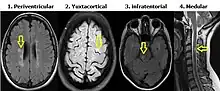

Criterios de Diseminación en espacio de Swanton

Lesiones desmielinizantes en diferentes regiones del sistema nervioso central. Se requiere al menos una lesión en Resonancia Magnética en secuencia T2 en por lo menos dos de las siguientes 4 áreas: